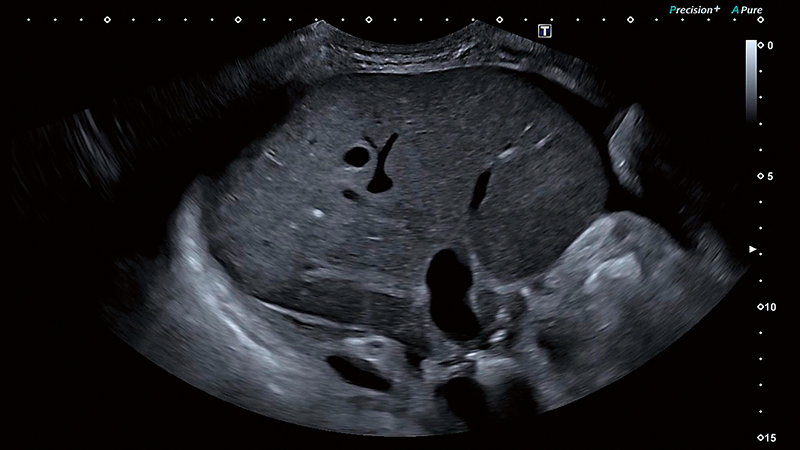

Раннє виявлення

УЗД Aplio може забезпечити чудову якість зображення та контрастну роздільну здатність. Це дозволяє клініцистам покращити раннє виявлення морфологічних змін та патологій.